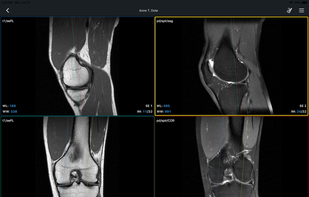

Starviewer is described as 'It is a medical imaging viewer capable of connecting to PACS servers, and/or open locally stored DICOM files in a DICOMDIR as well as stacks of regular image slices (PNG, TIFF, JPG...)' and is a DICOM Viewer in the sport & health category. There are more than 10 alternatives to Starviewer for a variety of platforms, including Mac, Windows, Linux, iPhone and iPad apps. The best Starviewer alternative is Weasis, which is both free and Open Source. Other great apps like Starviewer are Horos, 3D Slicer, RadiAnt DICOM Viewer and OsiriX.